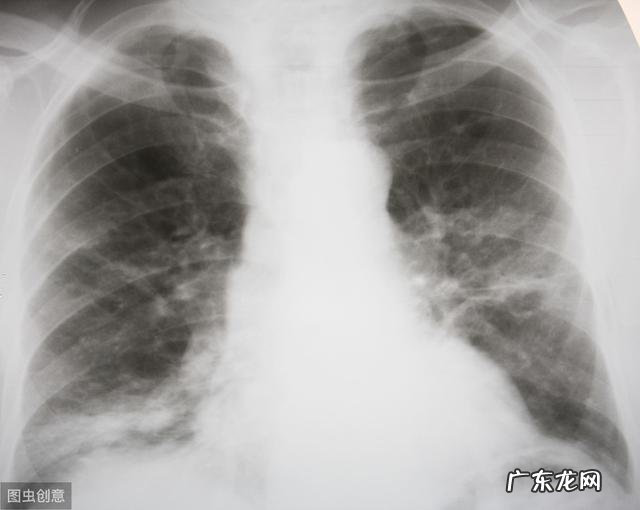

这次新冠肺炎疫情爆发后 , 很多病人发现去医院住院变得相对复杂 , 有些地方住院前要求做血常规 C反应蛋白(CRP) , 新冠病毒核酸检测 , 甚至做肺部CT 。这其中的C反应蛋白 , 大家可能觉得不太理解 , 做的意义何在 。其实C反应蛋白是一个急性期的炎症指标 , 升高提示存在炎症反应 。

病毒性感染者C反应蛋白大都正常或轻度升高(通常不超过50mg/L , 极少超过100mg/L) , 故可用来鉴别细菌感染和病毒感染 。不过此次新冠肺炎患者多数会出现C反应蛋白升高 , 这也是入院前检查的原因 。